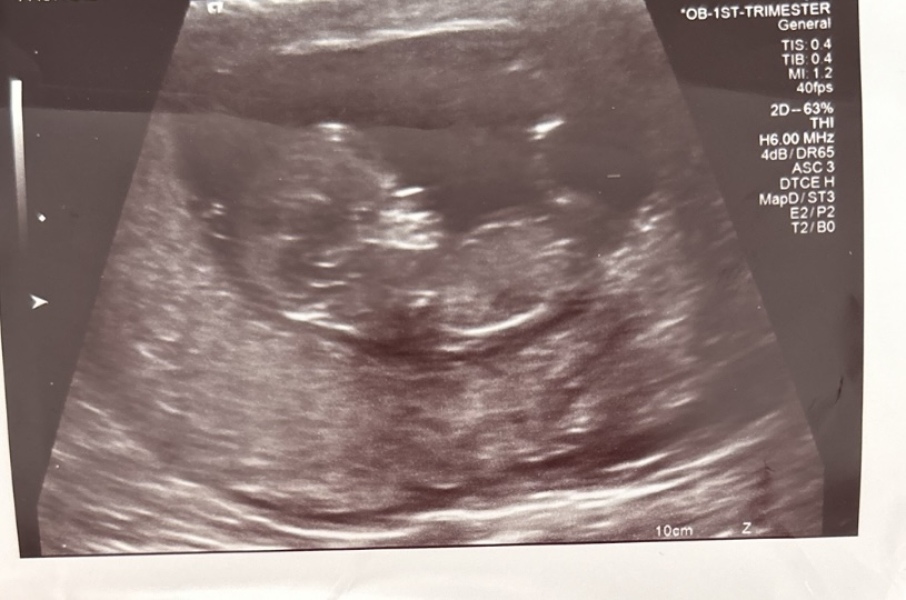

Aleera · 26/05/2020 18:01

Hi have had my 12 week scan and am dying to find out what the gender is can anyone guess what I could be having.

Really hoping for a girl and keep dreaming I'm having a girl and my 2 year old keeps saying it's girl.